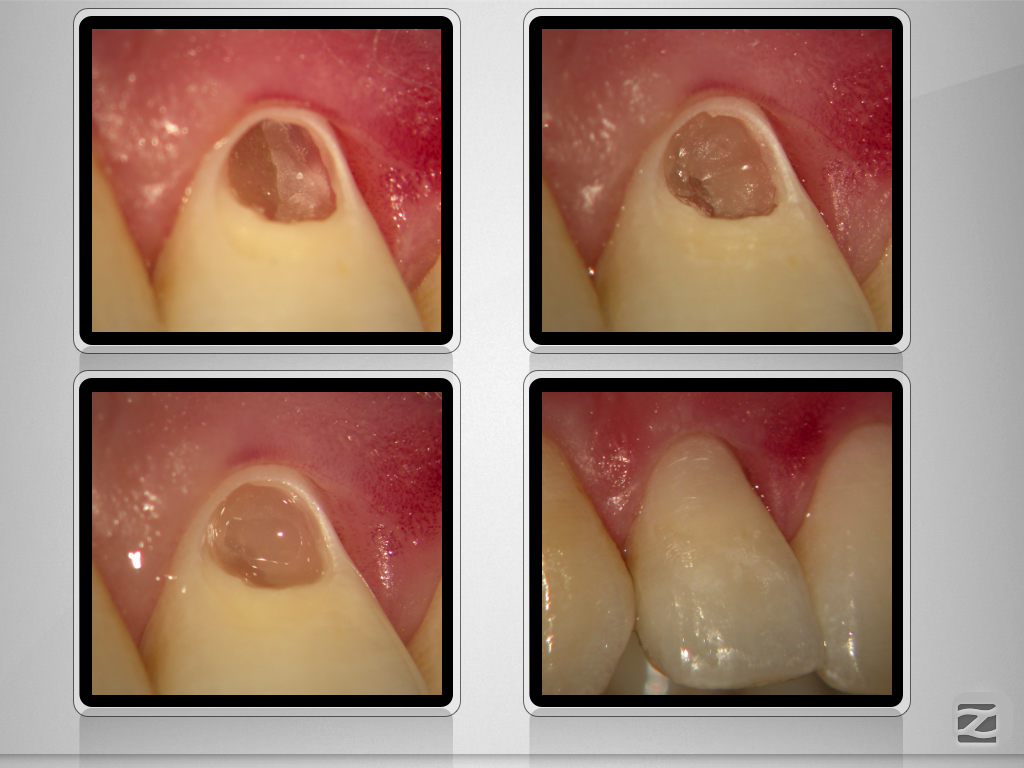

Externe Resorption mit Perforationen